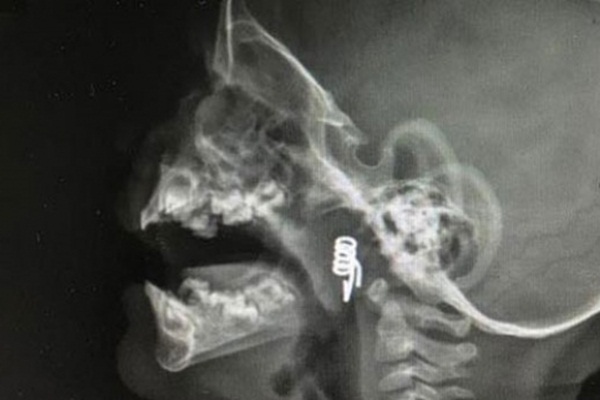

Nevşehir’de 1 yaşındaki minik bebeğin nefes borusuna saplanan mandal yayı başarılı bir operasyonla çıkartıldı. Operasyonun ardından yapılan kontrollerde bebeğin durumunun son iyi olduğu bildirildi.

Nevşehir'in Derinkuyu ilçesinde ikamet eden Yılmaz ailesinin henüz 1 yaşındaki bebekleri Özlem İlayda Yılmaz elinde oynadığı mandalı ikiye ayırdı ve yayı boğazına kaçtı. Baba Yaşar Yılmaz, olayı fark eder etmez kızının boğazına kaçan yayı çıkartmaya çalıştı. Baba Yılmaz, yayı çıkartamayınca aile hemen Nevşehir Devlet Hastanesi Acil Servisine başvurdu. Nöbetçi doktorlar tarafından ilk müdahalesi yapılan minik Özlem'in, Kulak Burun Boğaz Uzmanı Dr. Ahmet Cevatzade tarafından hemen ameliyatı alınmasının ardından boğazına kaçan yay çıkartıldı.

Baba Yaşar Yılmaz kızının kontrolü için geldiği devlet hastanesinde olayı anlatırken kızımın yaşamasını “Önce Allah sonra doktorlarımız sağladı” dedi. Baba Yılmaz, “O gün akşam saatlerinde çocuğum elinde mandal yayı ile oynarken mandalı ikiye ayırıp yayı sökmüş. Ağzına alıp yay ile oynadığını fark ettim. O an hemen parmağımla müdahale ettim ama yayı çıkartamadım. Yay boğazın ilerisine kaçmış. Hemen Nevşehir Devlet Hastanesi Acil Servisine geldik. Acil doktorlarımız çocuğumun filmlerini çekti. Hocamız sağ olsun hemen müdahale etti. Nevşehir Devlet Hastanesi çalışanlarına çok teşekkür ederim” dedi.

Konuya ilişkin açıklama yapan Dr. Cevatzade, minik Özlem'in sağlık durumunun son derece iyi olduğunu belirterek, "Şu anda çocuğumuzun sağlık durumu gayet iyi. Çocuğumuz şanslıydı. İlk mandalın yayını yuttuğunda babasının müdahalesiyle yay hava yoluna kaçmamış o yönden çok şanslıydı. Çocuk acile getirdiklerinde hemen ameliyata alarak yayı çıkarttık. Şuanda durum çok iyi. Bu tip yabancı cisimler özellikle hava yolunda çok büyük sıkıntılar yaşatıyor. Aileler bu tip şeyler ellerine vermesinler" şeklinde konuştu.